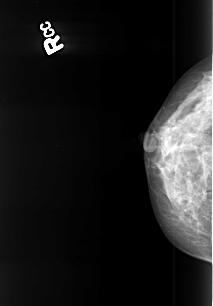

B_3418_1.RIGHT_MLO

RIGHT_CC LINES 3976 PIXELS_PER_LINE 2768 BITS_PER_PIXEL 12 RESOLUTION 50 NON_OVERLAY

RIGHT_MLO LINES 4144 PIXELS_PER_LINE 2784 BITS_PER_PIXEL 12 RESOLUTION 50 NON_OVERLAY